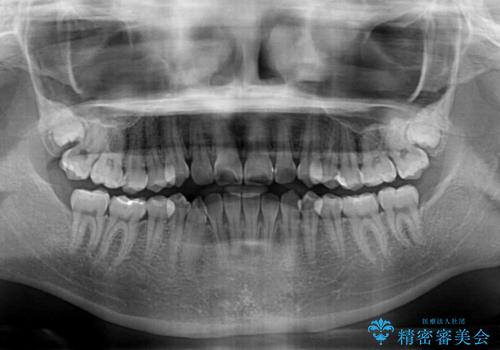

- 前歯のデコボコと奥歯の咬み合わせを気にして来院された患者様です。

右側の奥歯は、上が外側に転位した鋏状咬合を呈しており、前歯のデコボコ改善と並行して咬み合わせを改善していく必要がありました。

ワイヤー矯正を選択されたため、鋏状咬合を確実に改善するために補助装置を併用することとしました。